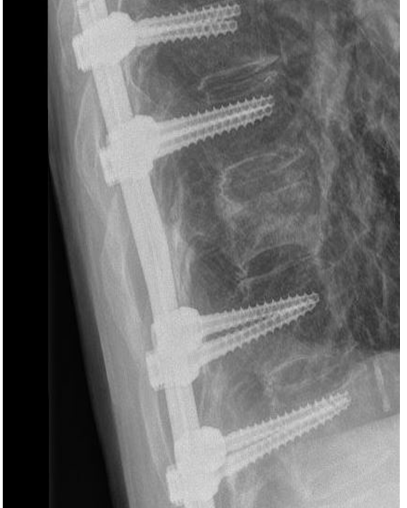

Bij een instabiele breuk is dit risico wel aanwezig en daarom is een stabiliserende operatie noodzakelijk. De revalidatie zal grotendeels overeenkomen met de revalidatie na een stabiele breuk zonder operatie.

Controle polikliniek

Na 6 weken komt u voor controle in de polikliniek bij uw behandelend arts. Er wordt een röntgenfoto gemaakt van uw rug en de voortgang van het herstel wordt beoordeeld. U krijgt advies over de opbouw van de oefeningen en hoe om te gaan met uw rug tijdens dagelijkse

activiteiten, werk en sport. Het advies is om de coördinatie en de kracht van uw rugspieren, buik- en flankspieren te trainen. Meestal wordt u hiervoor verwezen naar een fysiotherapeut.